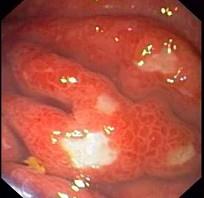

问题 男性,38岁,反复上腹痛6月,疼痛无明显规律性,应用抗酸剂治疗腹痛有时能缓解,伴腹胀、食欲减退、消瘦明显,查体:贫血外观,左锁骨上未触及肿大淋巴结,腹部可触及一包块。粪隐血阴性。胃镜检查如下图:该病人最可能的诊断是 ( )

选项 A.胃黄斑瘤 B.胃癌 C.胃溃疡恶变 D.胃泌素瘤 E.胃淋巴瘤

答案 E